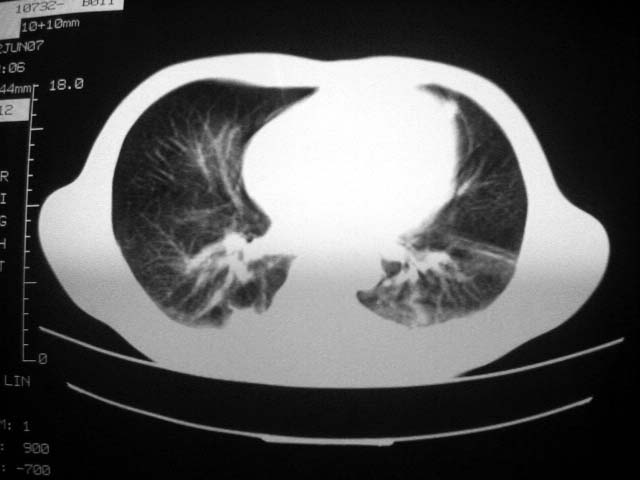

标题: CT7988D:近期图像 出乎意料!

从ct7988c 至今未用任何抗生素及抗痨药,维持保肝治疗。患者低热、咳血渐消失。

07年6月22号复查

前几次大家认为是转移癌,但此次复查病灶却明显吸收好转,不支持诊断。请大家讨论。[emb10]

近2个月病灶变化较大,应是感染性病变,首先考虑金黄色葡萄球菌感染。

根据前后片比较应该考虑迁徙性肺脓肿,回帖相差甚远是因为前后片变化太大出乎大家意料之外,这就是影象诊断要结合临床复查对比的必要性,

回顾既往片,病变明显吸收,缩小,未经治疗,不支持肺转移瘤,可能为肺结节病或韦格氏肉芽肿